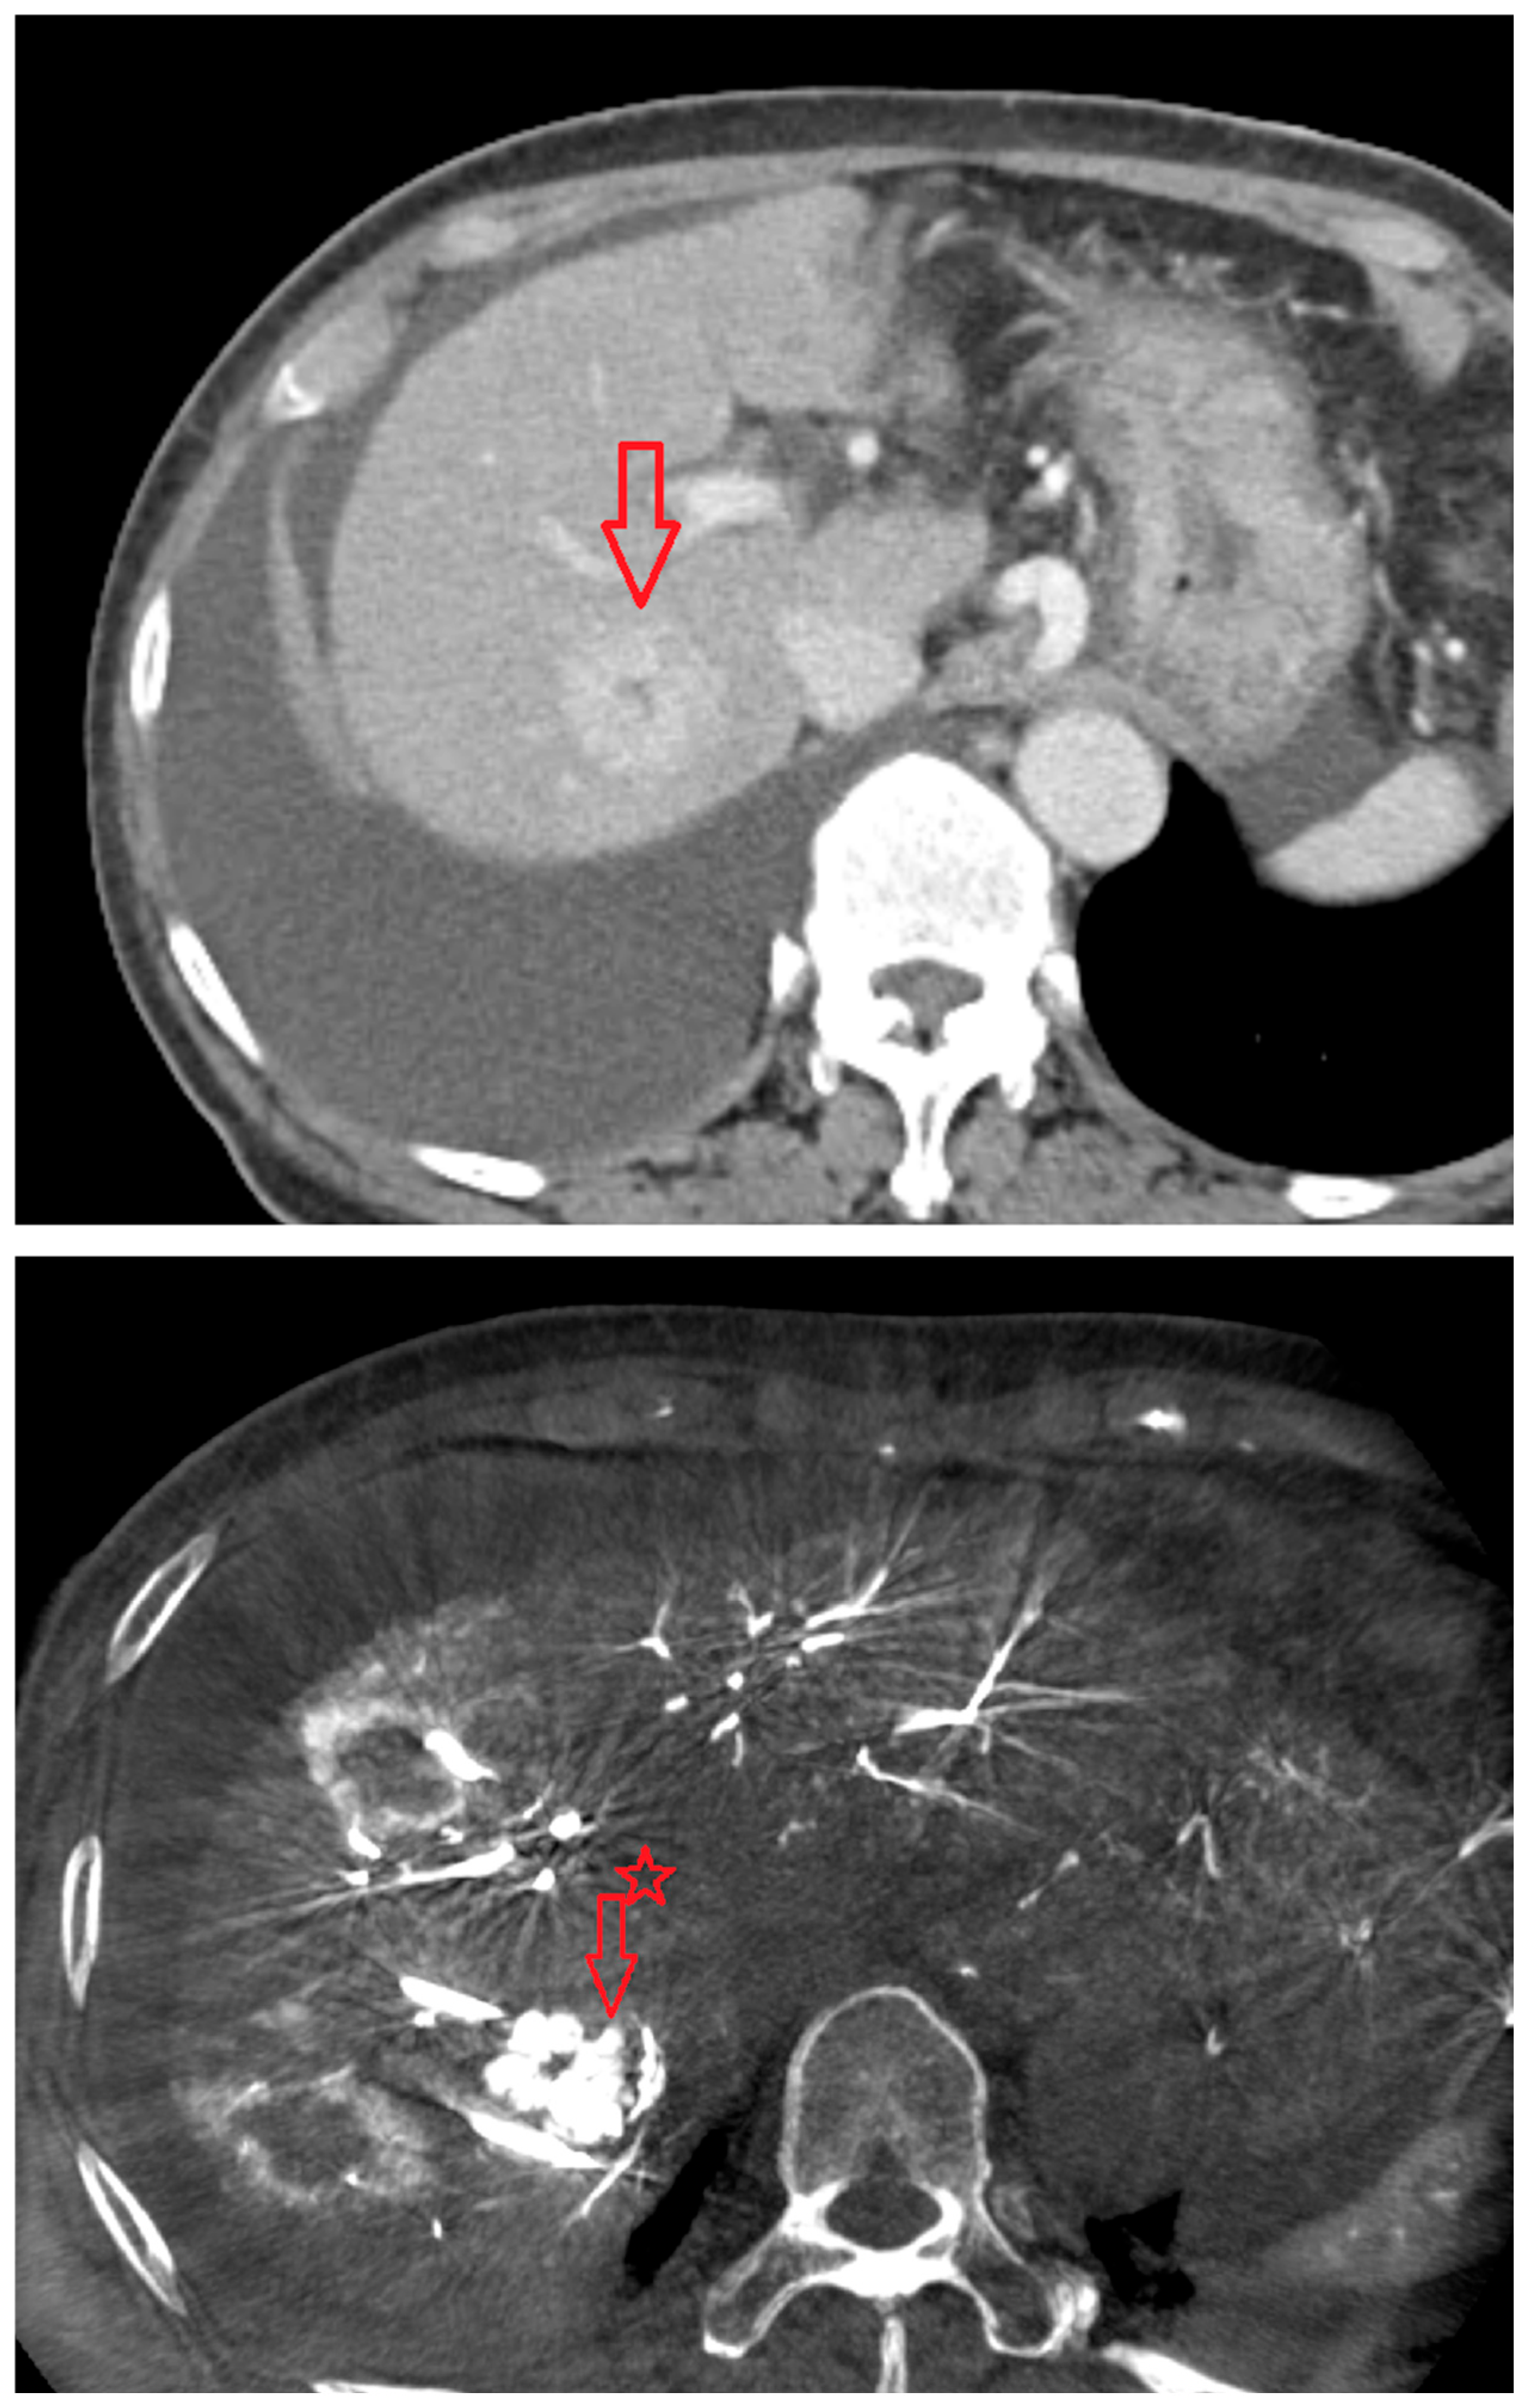

Figure 2. CT images from a patient with hepatocellular carcinoma undergoing angio CBCT-guided RFA. (Top): pre-procedural CT (portal venous phase; lesion 128.7 HU, red arrow = HCC mass). (Bottom): intraprocedural angio CBCT (lesion 1499.7 HU, red arrow with star = HCC mass). ΔHU = 1298.0 HU. (intra lesion − intra background) − (pre lesion − pre background).

As shown in Figure 1, angio-CBCT allows for higher visibility of the target mass, as reflected in the ΔHU values. This can be visually confirmed in several cases. Representative cases in Figure 2 and Figure 3 demonstrate how the target mass is much more conspicuous to the operator on angio-CBCT compared to pre-procedural CT. In Figure 4, a mass, which was nearly invisible on pre-procedural CT, was identified through angio-CBCT, aiding the targeting process. Figure 5 shows a case where a mass with discordance between USG and CEUS was confirmed using angio-CBCT, leading to needle repositioning and achieving complete ablation. Finally, Figure 6 illustrates a case where a residual tumor was identified on angio-CBCT and re-ablation resulted in complete ablation.